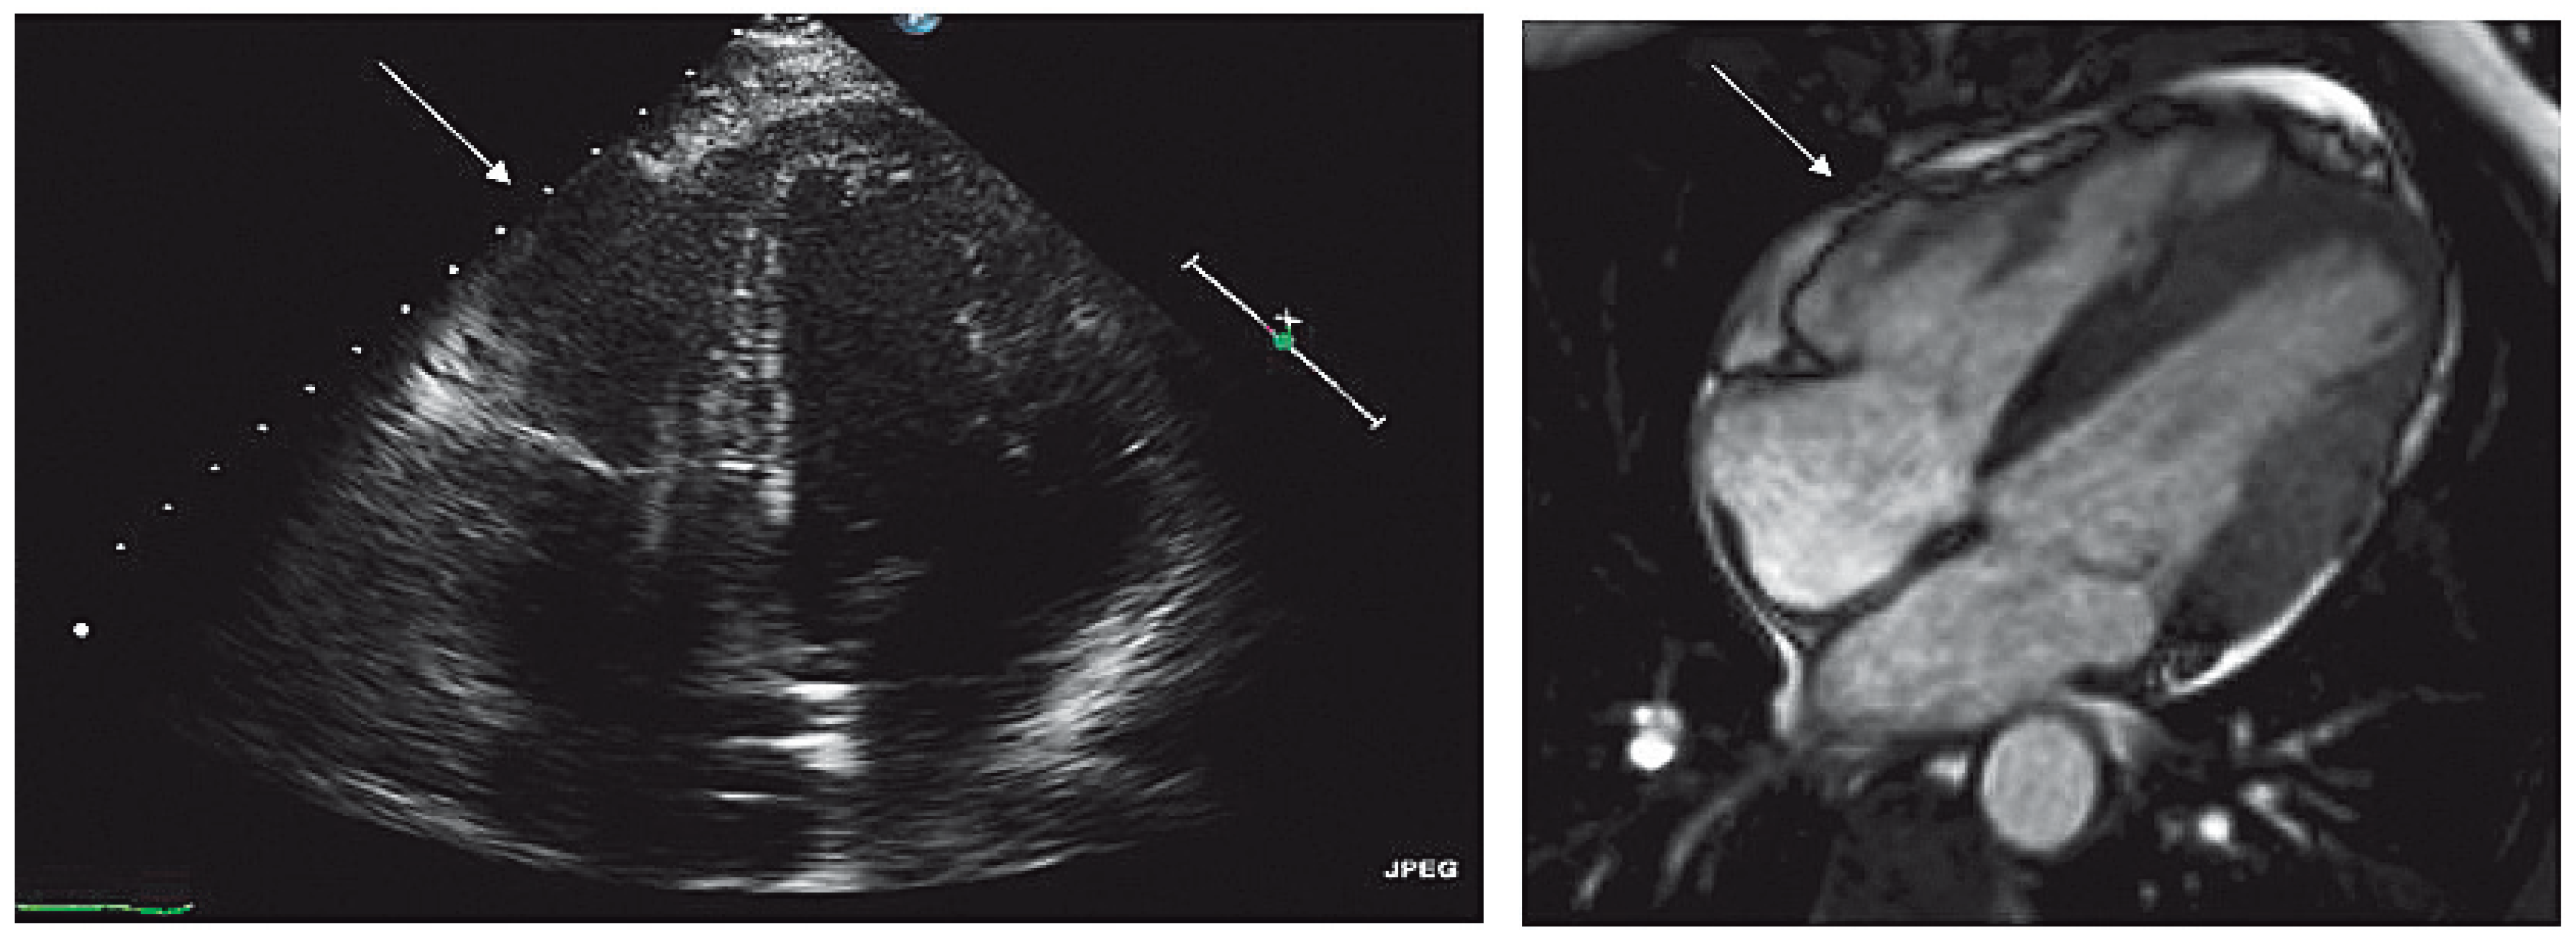

Echokardiographie, kardiale Magnetresonanz (CMR) und RV-Angiographie